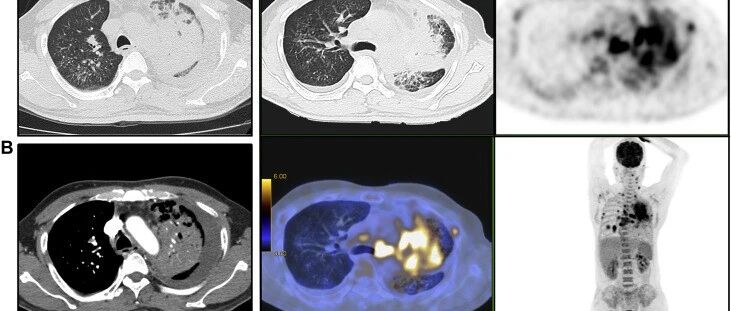

52岁男性,发热、咳嗽、胸痛、胸腔积液和左肺不张11个月,到底是什么原因?

来源:医脉通呼吸频道

时间:2020-10-09